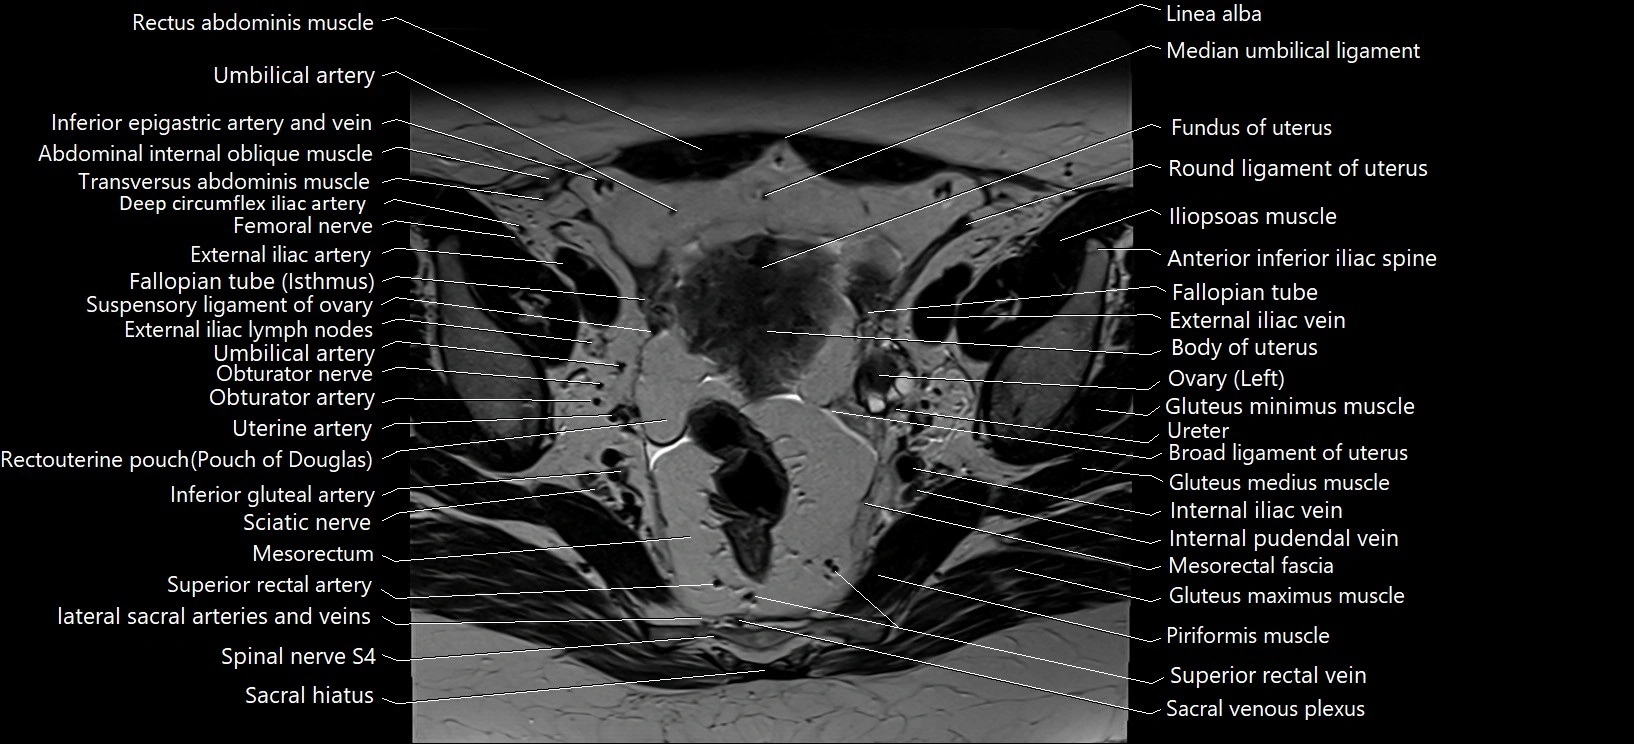

- Body of uterus

- Broad ligament of uterus

- External iliac artery

- External iliac vein

- Fallopian tube

- Fundus of uterus

- Gluteus maximus muscle

- Gluteus medius muscle

- Gluteus minimus muscle

- Iliopsoas muscle

- Inferior mesenteric vein

- Internal iliac vein

- Internal pudendal vein

- Left ovary

- Median umbilical ligament

- Mesorectal fascia

- Mesorectum

- Obturator externus muscle

- Piriformis muscle

- Rectouterine pouch (pouch of Douglas)

- Round ligament of uterus

- Sciatic nerve

- Superior rectal artery

- Suspensory ligament of ovary